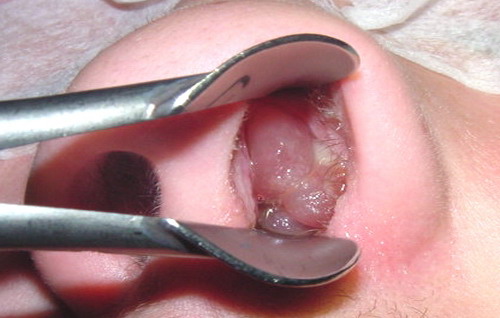

Obstrucția nazală, adică respiratul greu pe nas, respirație orală, secreții seroase sau muco-purulente, cefalee, și asocierea, uneori, cu astmul bronșic sau alte patologii imunologice sunt întâlnite. Sunt două forme : cu polipi nazali sau fără. Polipii sunt degenerescențe benigne ale mucoasei nazale în urma unor procese cronice, repetate de inflamație virală, bacteriană sau combinată la nivelul mucoasei nazale Dacă există și un teren atopic, adică o predispoziție a subiectului pentru alergii, atunci obstrucția nazala este mai importantă pentru că riscul de apariție a polipilor crește.

Până nu demult strategia terapeutică constă în tratament în primă fază, cu antinflamatorii, anticongestionante, antihistaminice, medicamente care stimulează drenajul și, dacă aveam semne de infecție bacteriană, antibiotic pentru 10 zile. Se mai folosesc și tratamentele cu corticosteroizi topici, adică administrați local, pentru 3 luni. Iar dacă aceste tratamente nu dau rezultate la dozele maximale se indică cura chirurgicală în cazul polipilor și a sinuzitelor fungice. Partea proastă pentru pacient este că foarte frecvent polipoza recidivează și astfel trebuie reintervenit chirurgical.